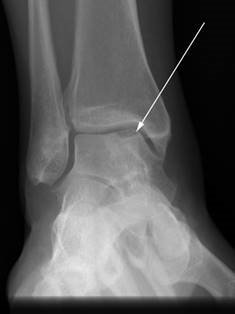

Hallux varus, characterized by medial deviation of the hallux, is an iatrogenic complication that is deeply frustrating for both the surgeon and the patient. It is typically the result of a "staged" error: over-resection of the medial eminence past the sagittal sulcus, combined with over-plication of the medial capsule and complete transection of the lateral collateral ligament. Flexible deformities can occasionally be managed with an extensor hallucis brevis (EHB) tenodesis, while rigid deformities inevitably require arthrodesis.

Image

Hallux Varus 2 - 8% Over-resection of medial eminence; Over-tightening of medial capsule; Aggressive lateral release. Early: Taping/splinting. Late: EHB tendon transfer; Medial capsule release; MTP Arthrodesis.